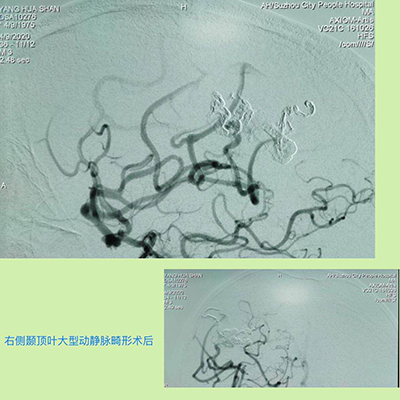

就在杨先生一家人感觉无望时,在一位病友的推荐下,找到了马修尧主任。在杨先生住院后的几天里,马修尧主任、任超、刘彬副主任,认真阅读了杨先生的外院检查CT、MRI和MRA等所有的影像资料,考虑是脑动静脉畸形,由于病灶巨大,直经接近7.0cm,且位于重要脑功能区,治疗上稍有不慎,便会导致肢体瘫痪甚至危及生命。马修尧主任认识到手术的高度风险,深感责任重大,带领团队积极查阅国内外相关文献,主动与省内外脑血管病知名专家深入交流,探讨治疗方案,并组织了由医务科、心血管内科、介入导管室等相关科室组成的专家治疗团队,组织多学科讨论,集思广益。经过严密细致的评估,最终为杨先生制定了最优的手术方案。

马修尧主任表示:针对颅内大型动静脉畸形,目前治疗手段主要有外科开颅手术切除和血管内介入栓塞两种方案,因其风险大、难度高,并发症多,对于手术医生来说是一个巨大的挑战。该手术的圆满完成,标志着我院复杂脑血管病诊治技术水平,走在了全省前列。